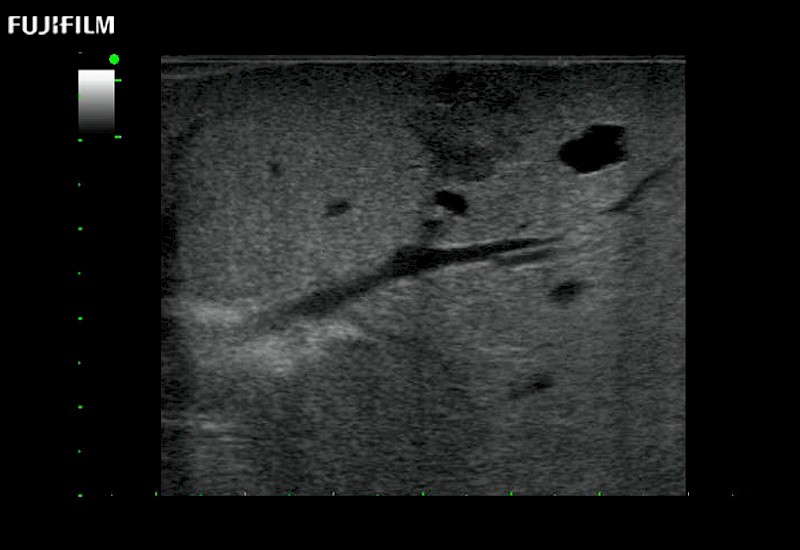

for use during general and laparoscopic procedures: Tumor localization & staging, Ablation, Resection, Biopsy, Transplant, Abdominal exploration, Robotic surgery

Our dedication to Laparoscopic Surgery allows us to offer superior image quality, outstanding system reliability and intuitive use of cutting edge technology.